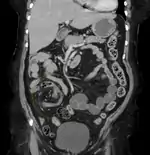

Coronal view of sigmoid volvulus with "whirlpool sign"

CT scan of a small bowel volvulus. It shows two juxtaposed segments of narrowing, which is the spot of mesentery rotation. The other signs indicate strangulation.

CT scan of a cecal volvulus